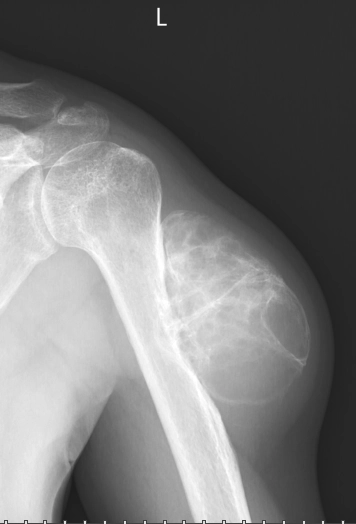

Sokan kérdezik, miért vagyok ennyire biztos a belső erőforrások erejében. A válaszom személyes: a munkám alapja nem csupán a diplomáimban, hanem a saját sorsomban rejlik. Ezt a folyamatot igazolja a két felvétel, amely sorsom két szélsőséges végpontját és a közte megtett utat mutatja meg:

Nem elmélet, hanem megélt valóság: ez a felvétel mutatja a kiindulópontot, ahonnan a belső munka és a bio-pszicho-szociális szemlélet segítségével vezetett az út a gyógyulásig.

A biológiai elakadás (2013)

Megjártam a legsötétebb mélységet. A 2013-as röntgenfelvétel nem csupán egy súlyos csontrák-diagnózis dokumentuma, hanem egy olyan válsághelyzeté, ahol a biológiai törvényszerűségek könyörtelenül megmutatkoztak. Ez volt az a pont, ahol beigazolódott: a valódi gyógyulás elképzelhetetlen a tudattalan minták és a bio-pszicho-szocio-spirituális összefüggések feltárása nélkül. Az orvosi protokollt nem vállalva döntöttem el: a belső erőforrásaimra támaszkodva találok vissza az egészséghez. Ott bebizonyosodott, hogy a gyógyulás feltétele nem a harc, hanem a megértés és a belső világ stabilitásának tudatos felépítése.